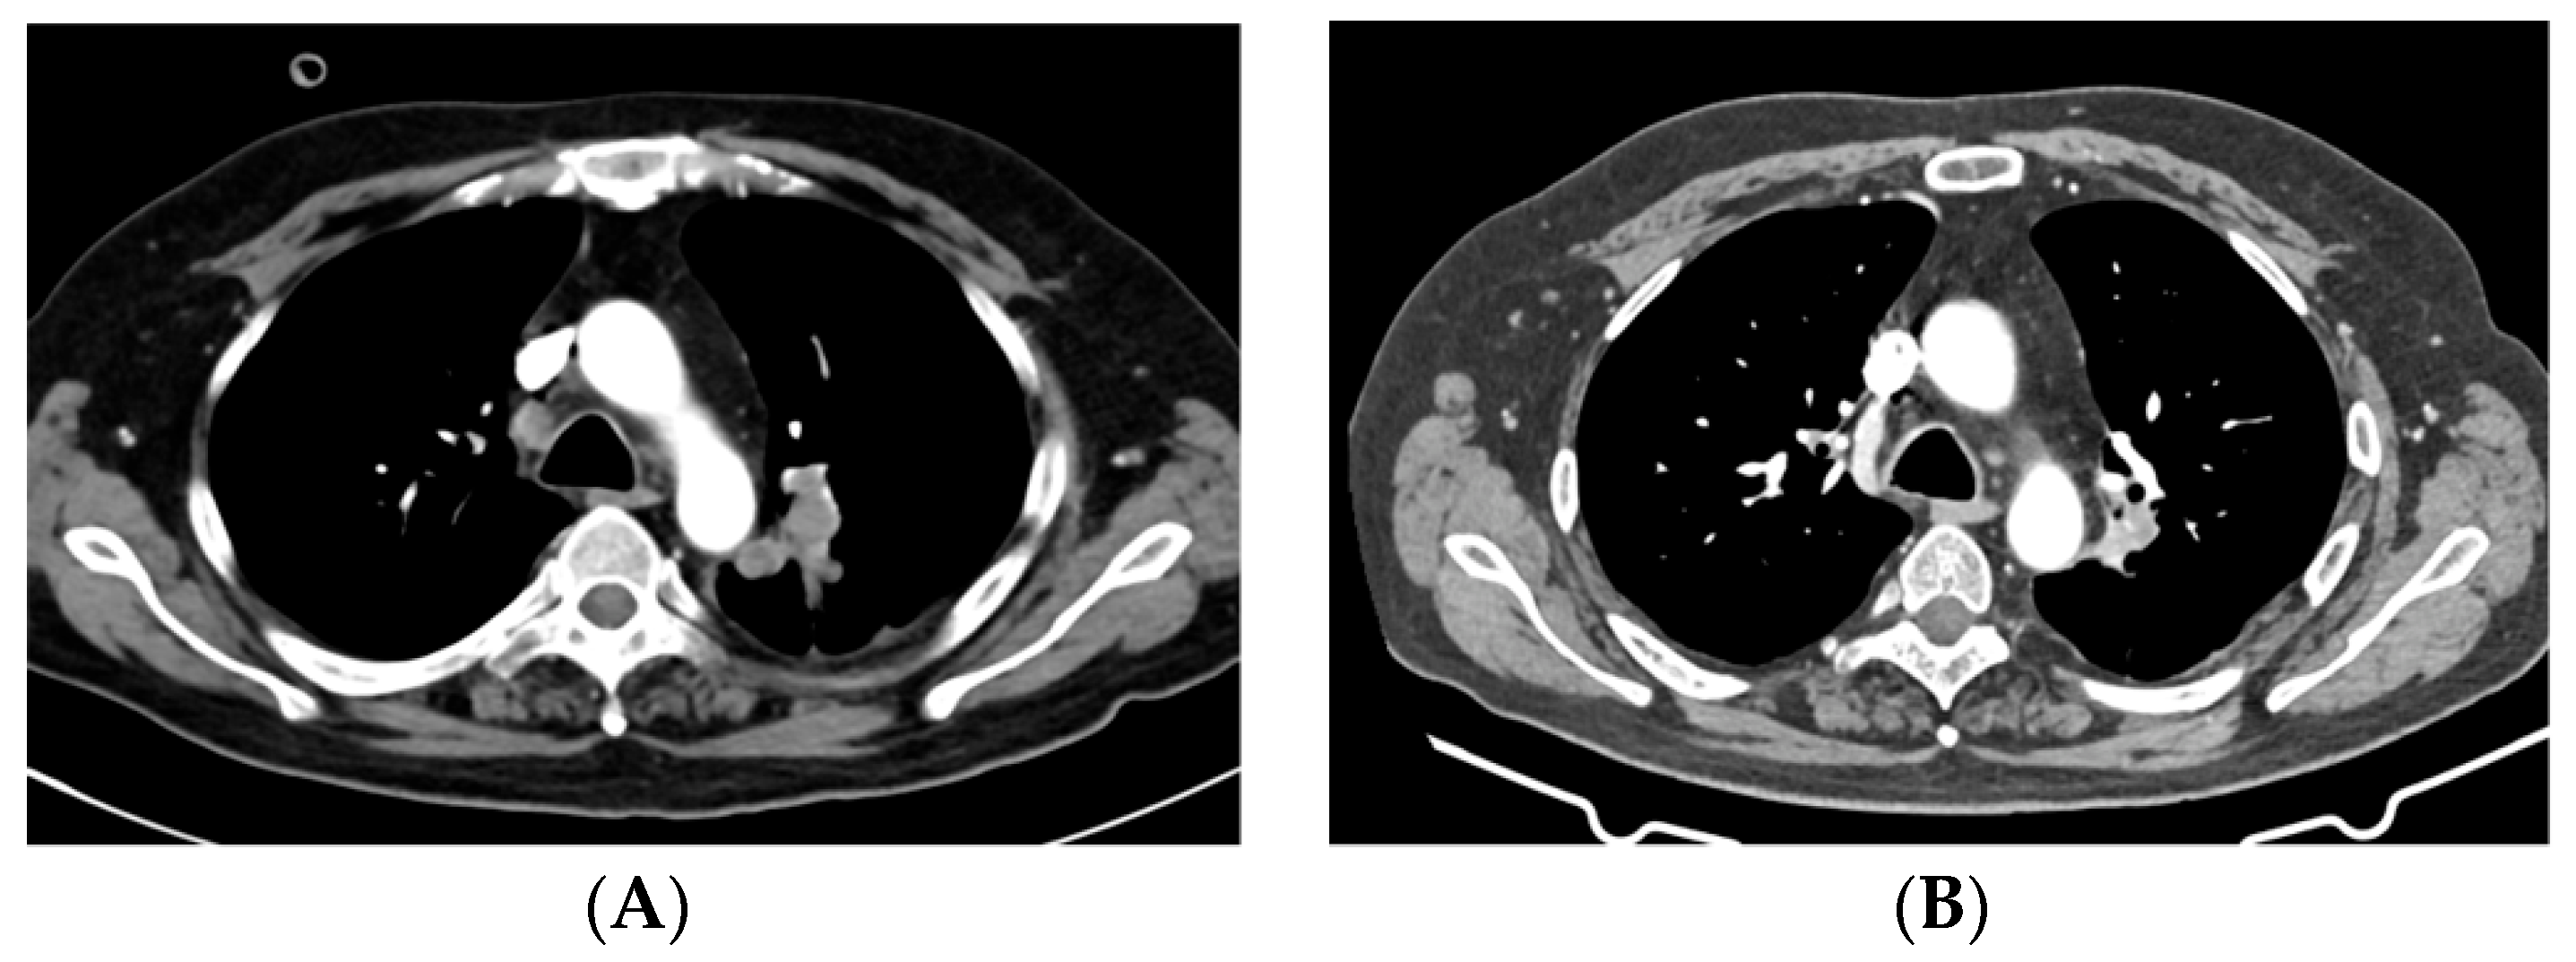

2.2. Case 2